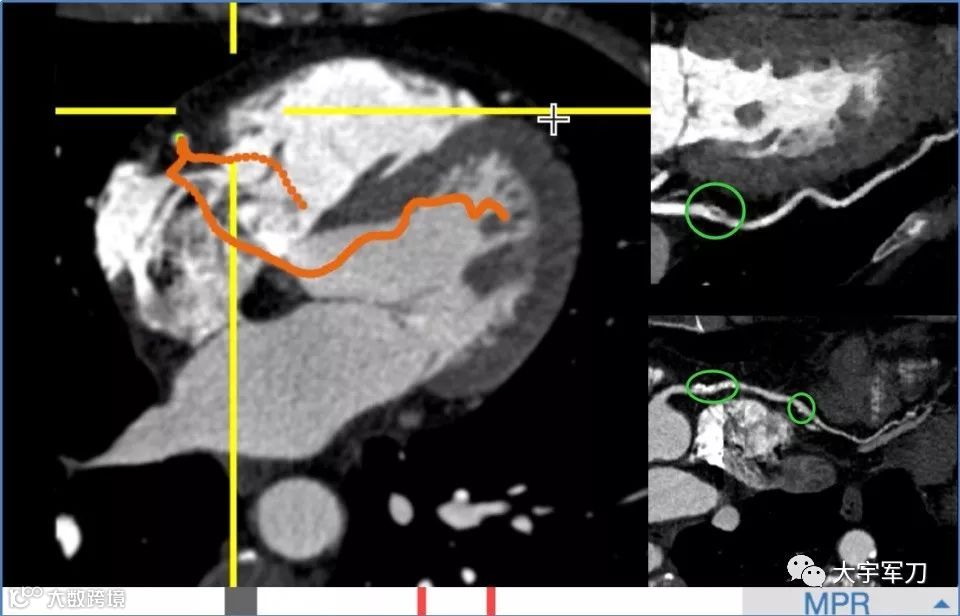

看看下面这张图:阿里AI在0.5秒内全自动提取的单根心脏冠脉,医生可从重建的影像上快速发现病灶。右上为血管上的软斑块,右下为钙化斑块。